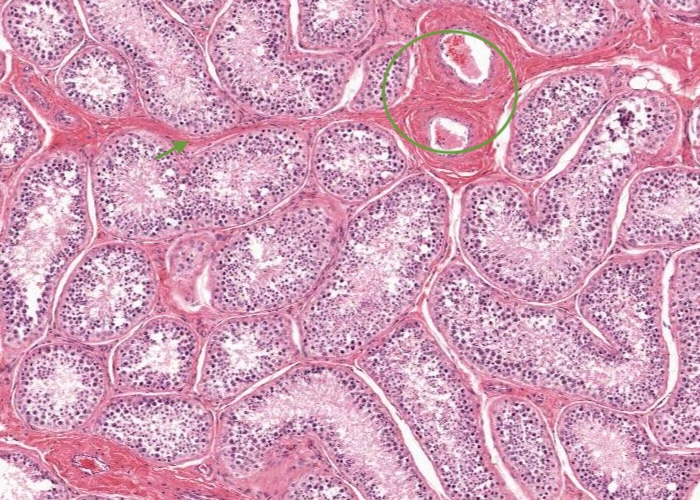

The coiled seminiferous tubules (which may be cut many times in transverse, oblique, or longitudinal section) consist of a sheath of fibrous connective tissue, a basal lamina and a complex stratified seminiferous epithelium.

Tubules are separated by loose connective tissue rich in blood vessels, lymphatics and nerves. This interstitial connective also contains interstitial cells of the testis (Leydig cells), and often shrinks during the preparation of histological slides and clear spaces (artefact) result in the section.

The tunic of the tubules, really a tunica (lamina) propria, is composed of thin fibrous connective tissue. An elongated nucleus of a myoid cell can be seen regularly within this tunic and these cells are referred to as peritubular contractile cells. Beyond the tunica propria extensive blood vessels and lymphatic vessels are present – and interstitial cells of the testis (Leydig cells).

Within spaces between seminiferous tubules are normal connective tissue elements and a rich vascular network, which is a continuation of the tunica vasculosa – the vascular capsule around the testis (an inner layer of the tunica albuginea).

Located within the connective tissue elements between the seminferous tubules are interstitial cells of the testis (Leydig cells). These are large, steroid-secreting cells and so they have extensive agranular (smooth) endoplasmic reticulum which accounts for their eosinophilic cytoplasm containing droplets of lipid (that are removed by the processing methodology for this H&E section).

From the mediastinum testis, connective tissue septa radiate from this capsule to subdivide the testis into approximately 250 compartments – the lobuli testis. A lobule is seen in this image with about 20 profiles (don't count them!) of seminiferous tubule/s bound by a connective tissue septum in the upper region of the image and another in the lower, left corner region of the image. Two large blood vessels are housed within the septum and will branch further and supply the seminiferous tubules.